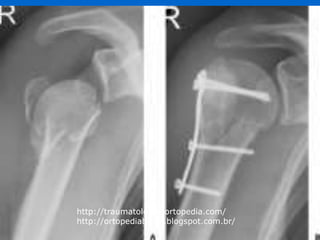

Tratamento cirúrgico

 # colo cirúrgico:

- Frequentemente instáveis

- Tenta-se redução(desvio aceitável e estávelconservador 3

semanas)

- Instáveis com mínimo desvio(aceitável)  tendência

peudoartrose/retardo consolidaçãott* cirúrgico e mobilização

precoce

- Fig 47.56

 # colo anatômico/ # colo cirúrgico

 Placa PFS(Pavilhão Fernandinho Simonsen)